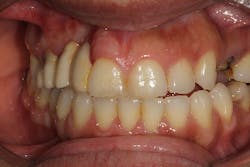

This patient presented with a long-standing edentulous area in the site of Nos. 6 and 7. She had lost both hard- and soft-tissue volume in the vertical and horizontal dimensions (figures 7 and 7a). Implant therapy was discussed as well as the option of multiple ridge augmentation procedures versus gingival ceramics. Although the patient has a low smile line, she was adamant about attempting to achieve a more proportional tooth length at final restoration. In addition, she complained about sensitive tissue underneath the pontic areas and an inability to clean her prosthesis. The periodontist and the patient decided to attempt to rebuild bony hard tissue and keratinized soft tissue. The patient understood the increase in finances and surgical procedures that would be involved.

The patient was referred to a periodontist who first augmented the edentulous site with a hard-tissue graft and membrane (figures 8 and 8a). Six months later, implants were placed in ideal positon (figure 9).

At the time of Stage II, six months after implant placement, a palatal roll soft-tissue augmentation was performed (figures 10 and 10a). Six weeks later, the area was provisionalized with new temporaries to develop soft tissue.

Two years after the patient first presented with her edentulous site, the case was completed and the patient was extremely happy (figures 11 and 11a).